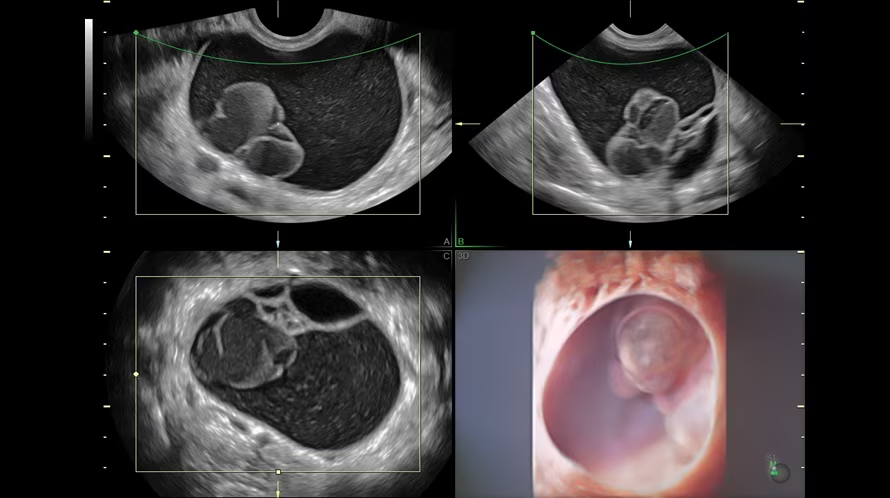

Дополнительные возможности объемной контрастной визуализации:

Внутриматочный контрацептив и миома матки с помощью технологии OmniView